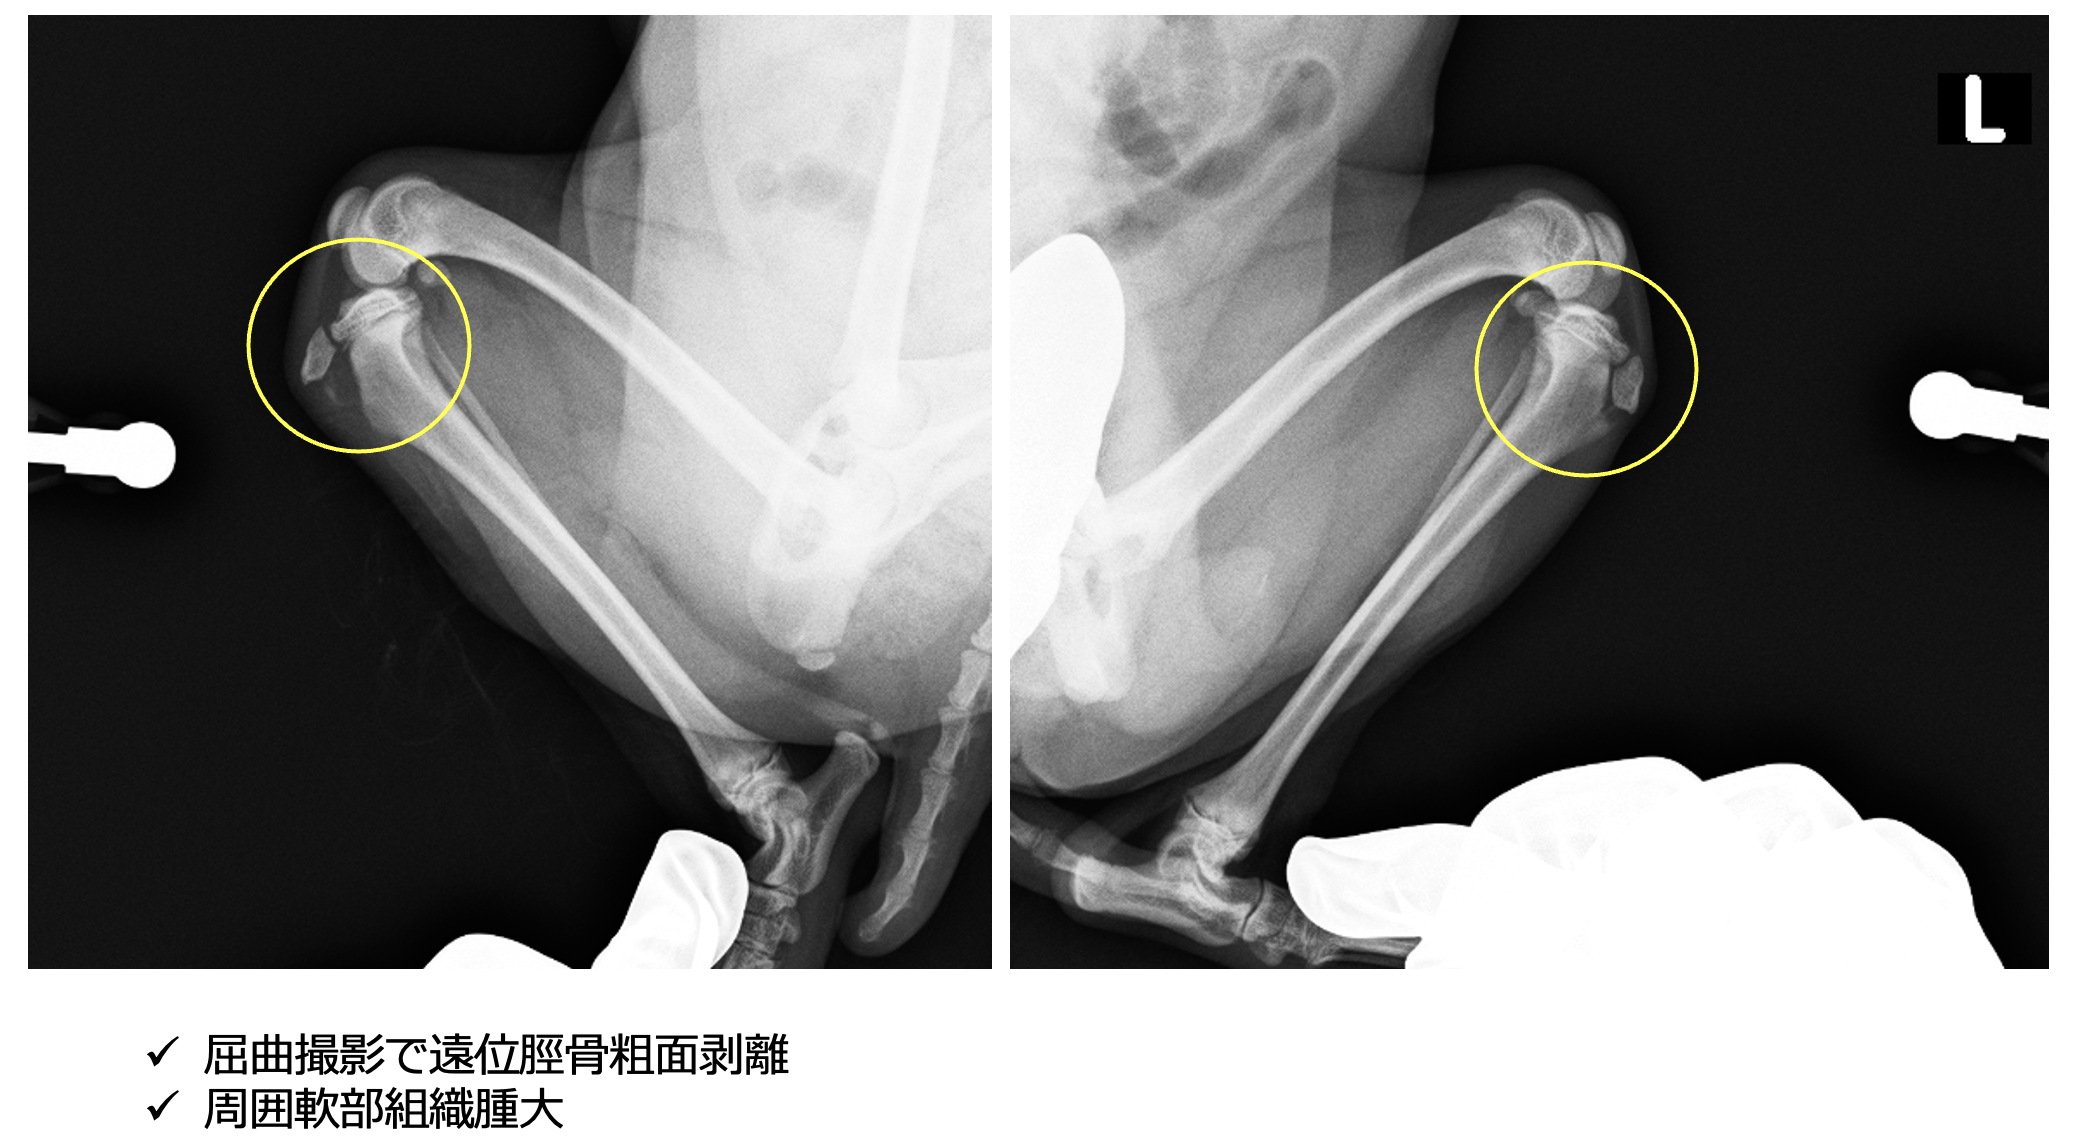

レントゲン検査より、脛骨粗面成長板の剥離

脛骨粗面とは、膝蓋骨が付着している脛骨の突起です。ここに成長板が残っているので、強い牽引力や急なジャンプなどで骨折することがあります。